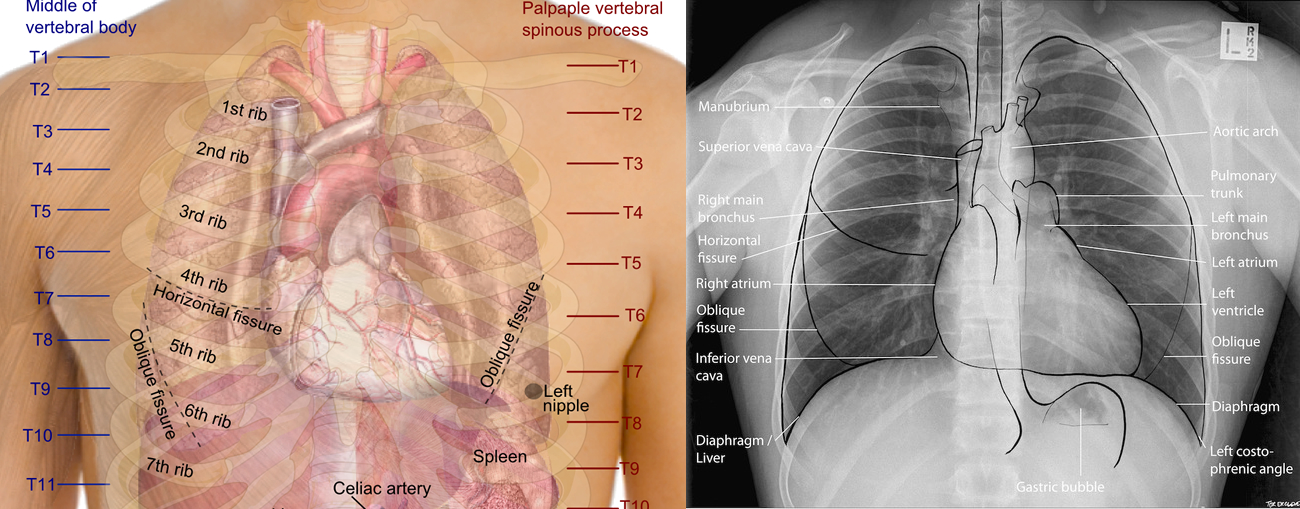

Chest radiograph Wikipedia Chest Meaning Wikipedia On this page, we’ll briefly take. The chest, properly called the thorax, is the superior part of the trunk located between the neck and abdomen. It is between the neck and abdomen. You can take the money from the chest. The trunk of the body from the neck to the abdomen; In mammals, the parts that make up the thorax. Chest Meaning Wikipedia.